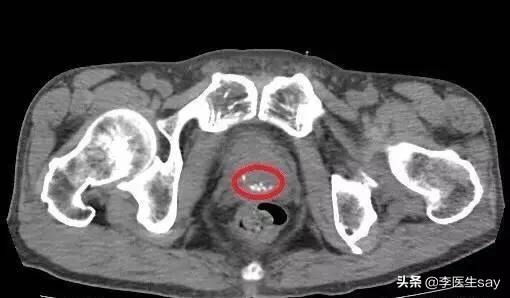

那好了,啥是前列腺真性结石?前列腺真性结石是指发生于前列腺腺管和腺泡内的强回声灶,较少见,这就是前列腺结石;啥叫假性结石?前列腺假性结石是发生在前列腺基质内的强回声灶,较多见,这就是前列腺钙化。

但是!其实目前的影像学根本无法区分前列腺钙化或是结石,最常用的超声也无法分辨钙化灶是位于前列腺腺泡内或腺管内,还是前列腺基质内。因此,超声检查通常将前列腺内强回声灶统称为前列腺局灶性钙化。